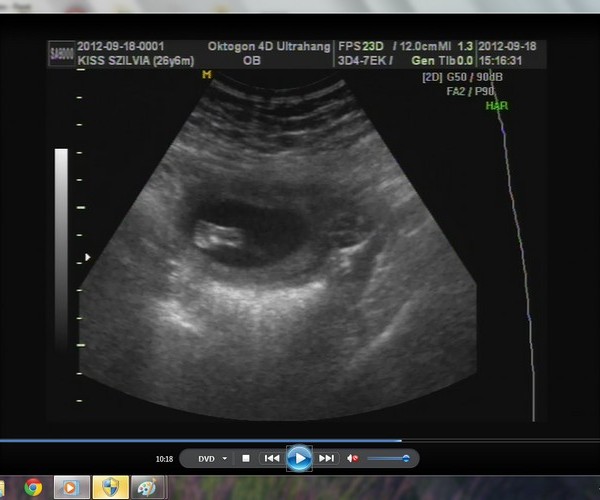

A képek először a babáról. :-) Kép 4d kedvenc :-)

Kép 2d

Kép tappancs

Kép és ott az a pici háromszög a lábikó között a kukac :-)